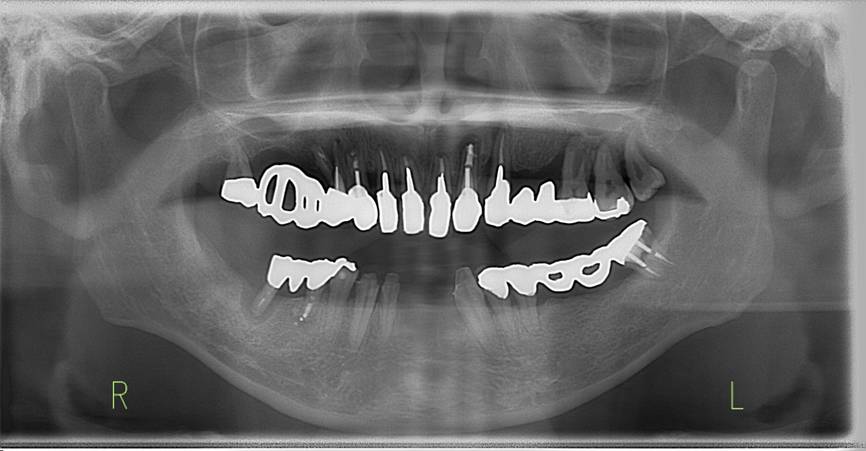

術前。すべての歯が歯周病の末期状態でブリッジ全体がうごいて噛めないとの訴え。右上の犬歯が腫れていました

固定式のブリッジが入っていましたが歯周病で動いています

下顎前歯部には歯石の沈着がみられます

術前パノラマレントゲン写真。根の周りが黒くなり、骨がなくなっていることがわかります